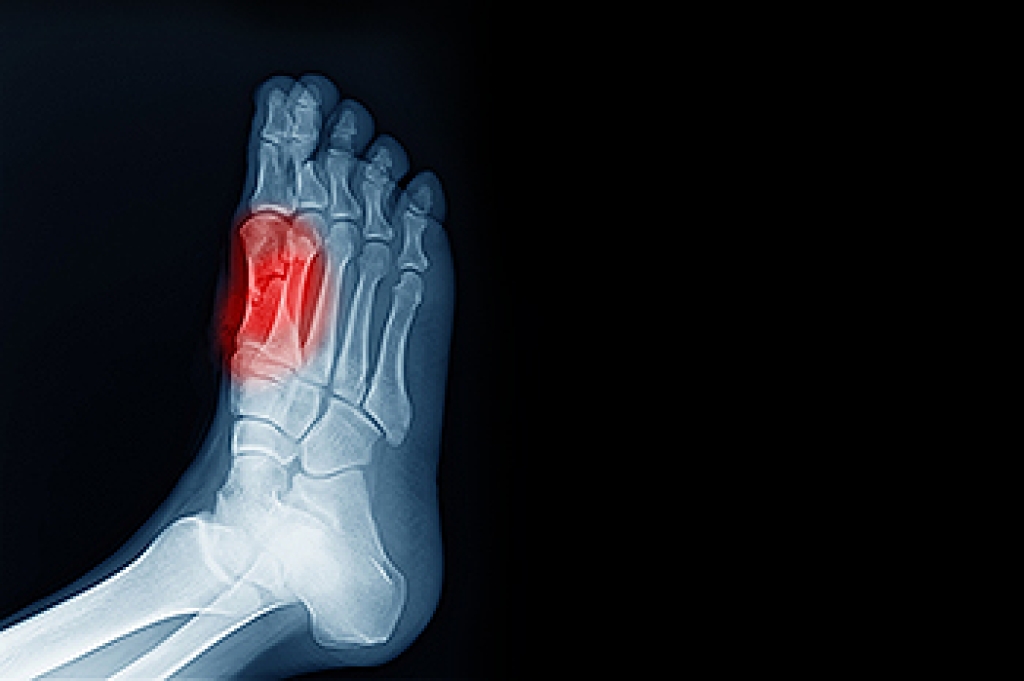

Sesamoiditis refers to inflammation of the sesamoid bones, the two small, pea-shaped bones located beneath the big toe joint within the tendons. These bones help the big toe move smoothly and bear weight during walking and running. Causes of sesamoiditis can include repetitive stress from activities that exert pressure on the forefoot, such as dancing or running, as well as wearing high heels or tight shoes that increase pressure on the ball of the foot. Symptoms include pain under the big toe, which worsens when bearing weight or bending the toe. Diagnosis involves a physical examination to assess tenderness and range of motion, in addition to imaging tests like X-rays to visualize the sesamoid bones and rule out fractures. Relief options include rest, cushioning pads, and footwear modifications. In severe cases, immobilization in a cast or surgical removal of the sesamoid bone may be necessary to alleviate pain and restore function. If you have pain under your big toe, it is suggested that you consult a podiatrist who can provide a diagnosis, and offer you a comprehensive treatment plan.

Sesamoiditis is a condition of the foot that affects the ball of the foot. It is more common in younger people than it is in older people. It can also occur with people who have begun a new exercise program, since their bodies are adjusting to the new physical regimen. Pain may also be caused by the inflammation of tendons surrounding the bones. It is important to seek treatment in its early stages because if you ignore the pain, this condition can lead to more serious problems such as severe irritation and bone fractures.

Foot stress fractures